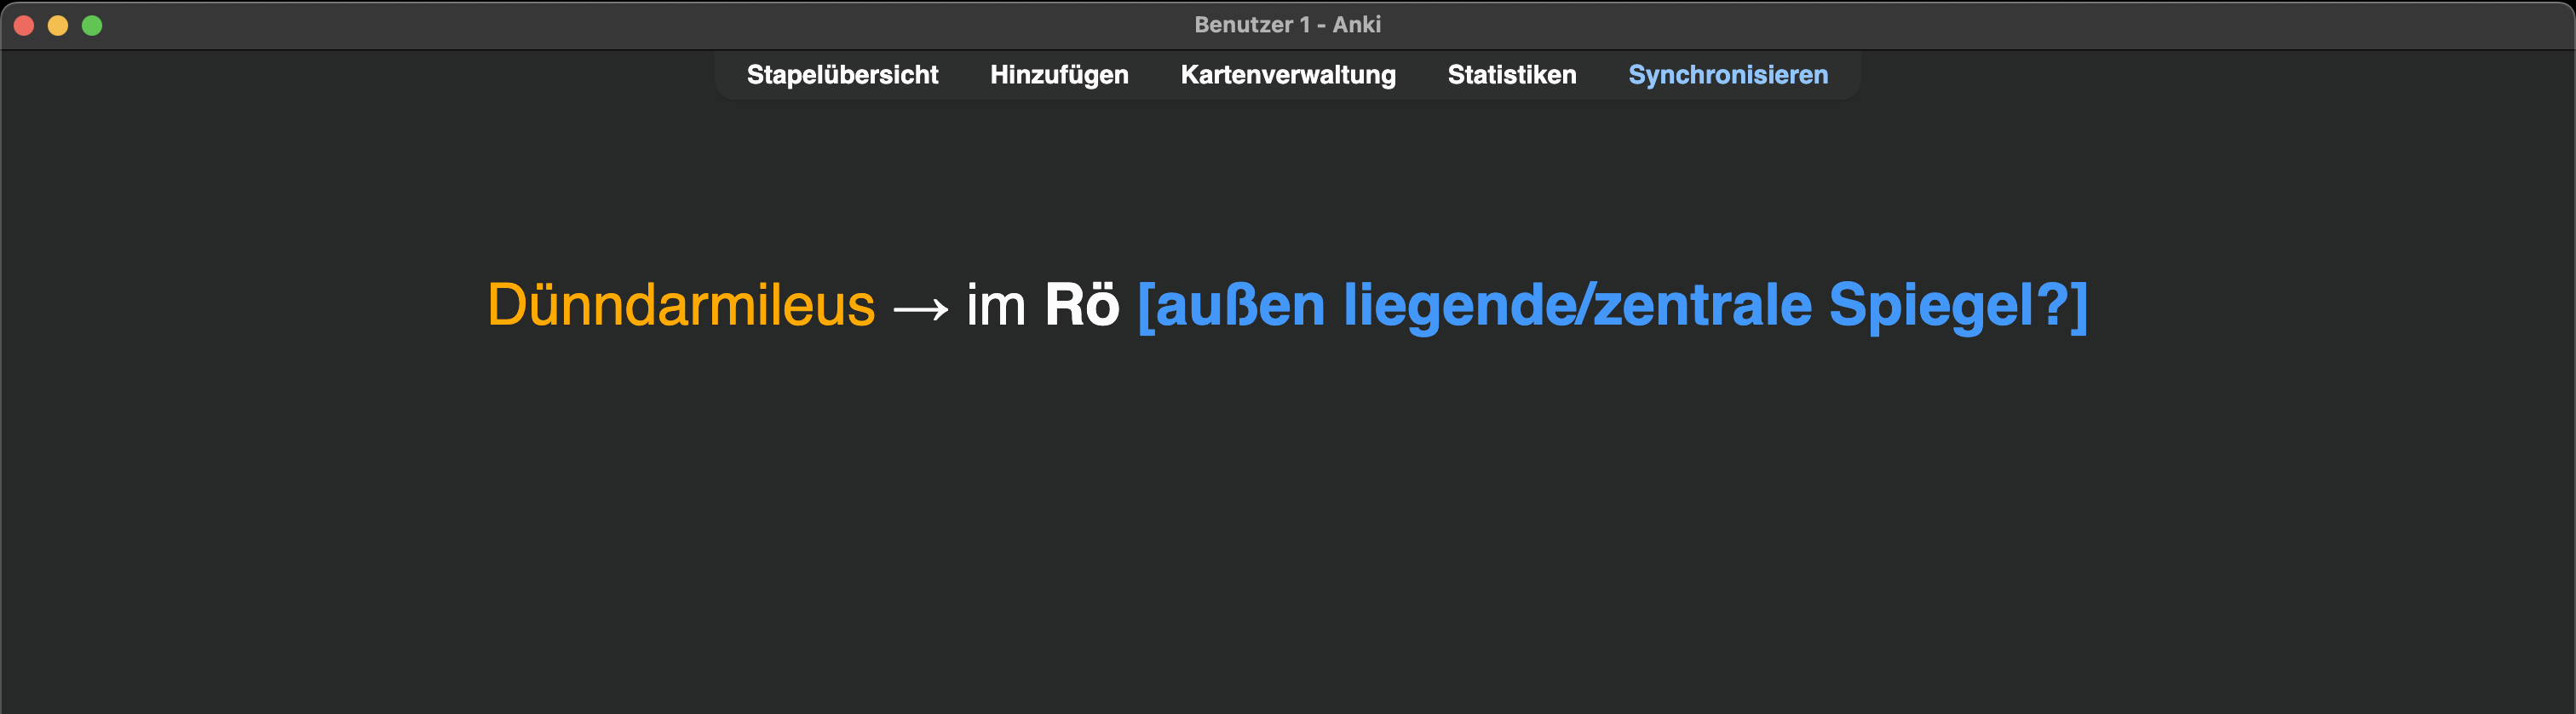

Ich konnte mir diese medizinische Information nur sehr schlecht merken:

Nach initialen erfolgreichen Wiederholungen (immer mit „Gut“ beantwortet) im weiteren Verlauf fünf Fehlversuche 😬. Also eine schlechte Karte! „Härter“ lernen bringt hier nichts; die Information ist einfach für mein Gehirn noch nicht appetitlich genug 🧀.

Also … Chunk🪓:

Bidirectional:

Das dann noch analog für den Dickdarmileus durchführen. Außer einer Karte werden also bis zu sechs. Erstmal mehr Zeitaufwand, aber auf lange Sicht ein Gewinn an Wissen und Zeit 🤑.